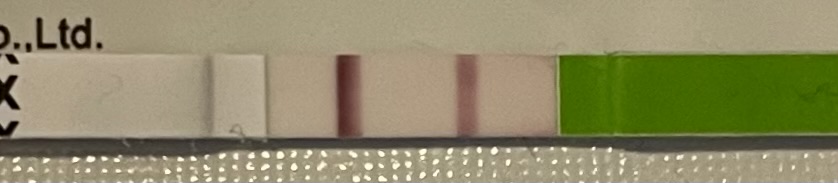

Tässä nyt ihan vertailun vuoksi tämän aamuinen dpo9 ja edellisen kemiallisen testi, jonka tein ekan kerran dpo14 ja sen jälkeen haaleni. En siis tiedä oliko tuon tummempi ollutkaan mutta sitä on turha nyt arvailla. Siihen verrattaen on tumma nyt, mutta aika näyttää  lämpöjen seurailua ajattelin jatkaa

@anita1 On kyllä tumma viiva dpo9. Mahtavaa että tiputtelu on pysynyt nyt pois Millä taktiikalla aiot jatkaa testailua? Kuva jos jatkat lämpöjen mittailua, se kiinnostaa erityisesti

@Summerwalk testasin aamulla ja yhtä vahva kuin eilenkin, oli tarkoitus vasta huomenna kokeilla mut ei pystynyt odottamaan. Tänään testikaupoille siis. Ehkä aavistuksen nopeammin piirtyi viiva testiin kuin eilen mutta ei todellakaan heti vaan sai hetken odotella ja sekös jännitti.

Ja lämmöt näyttää tältä, nyt on rintojen arkuus lisääntynyt, väsymys ja kylmyys myös.